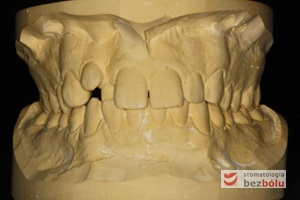

Młody 28-letni, pogodny, stale uśmiechnięty pacjent zgłosił się celem korekcji wad zębowych ograniczających pełną ekspresję uśmiechu. Głównym problemem był dodatkowy siekacz boczny (dwójka) po stronie prawej w łuku górnym. Dodatkowy ząb spowodował stłoczenia pozostałych zębów w łuku górnym oraz przesunięcie linii pośrodkowej. Obliczenia dostępnego miejsca dla siekacza bocznego wpłynęły na wybór zęba przeznaczonego do ekstrakcji. Usunięto dwójkę ustawioną dowargowo, zaś jej „siostrę bliźniaczkę” skierowaną w stronę podniebienia wprowadzono do łuku zębowego w drodze leczenia ortodontycznego. Problemem było szczelne zamknięcie szpary poekstrakcyjnej z powodu nadmiaru miejsca w kości. Wyrównano linię pośrodkową. Leczenie przeprowadzono jednym łukiem ortodontycznym górnym, dolny łuk zębowy nie wymagał założenia aparatu. Po zdjęciu zamków korekcję detali przeprowadzono z użyciem pozycjonera wykonanego w technice termoformingu. Stabilizację efektów leczenia zapewnił stały retainer klejony do powierzchni podniebiennych siekaczy górnych.